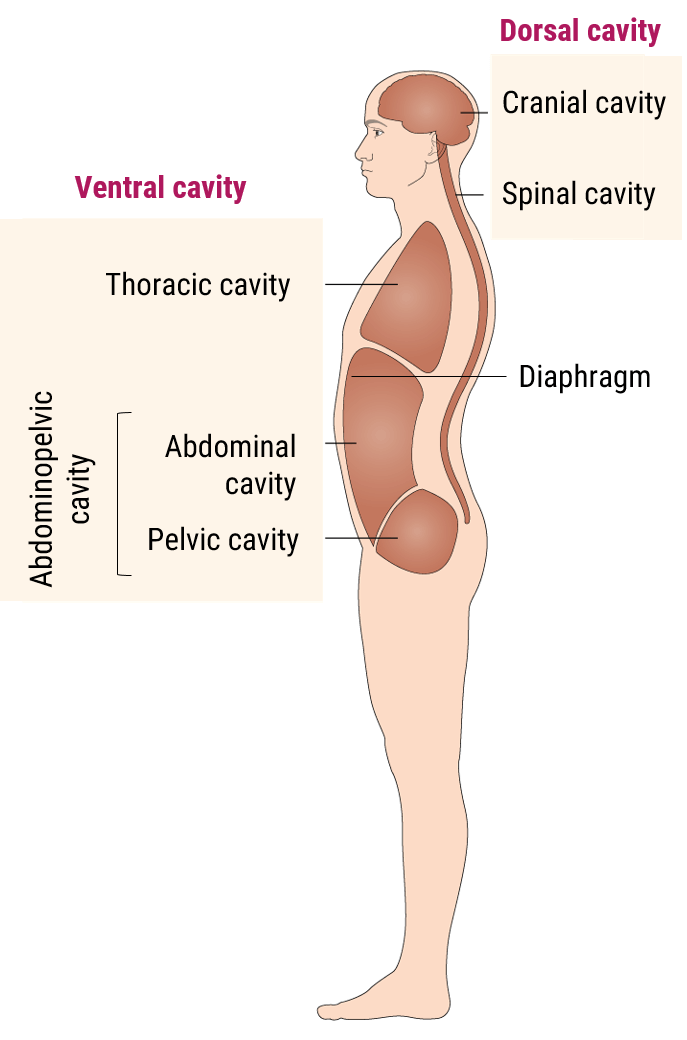

First, we shall know where is located the abdominal and pelvic cavity. The abdominal cavity is a large cavity found in the torso between thoracic pelvic cavities. It is separated from the thoracic cavity by the diaphragm.

A protective layer called the peritoneum, which plays a role in supporting organs, immunity, and fat storage, lines the abdominal cavity. As shown in this diagram, there is no overlapping partition between the pelvic and abdominal cavities.

Now let’s talk about the anatomy of the abdominal cavity and have a summary of the function of each organ.

The abdominal cavity is the largest body cavity in humans, it is lined by a thin, serous membrane called the peritoneum and contains different vital organs such as the liver, gallbladder, stomach, spleen, pancreas, kidneys, ureters, intestines, and the arterial and venous systems.